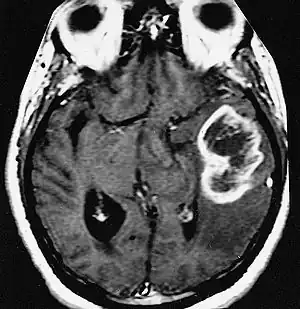

| An example of a ring-enhancement around a lesion in gliobastoma. In tumefactive multiple sclerosis, the ring-enhancement is open, not forming a complete ring. | |

Diagnosis of tumefactive MS is commonly carried out using magnetic resonance imaging (MRI) and proton MR spectroscopy (H-MRS). Diagnosis is difficult as tumefactive MS may mimic the clinical and MRI characteristics of a glioma or a cerebral abscess. However, as compared to tumors and abscesses, tumefactive lesions have an open-ring enhancement as opposed to a complete ring enhancement.[1] Even with this information, multiple imaging technologies have to be used together with biochemical tests for accurate diagnosis of tumefactive MS.[36]